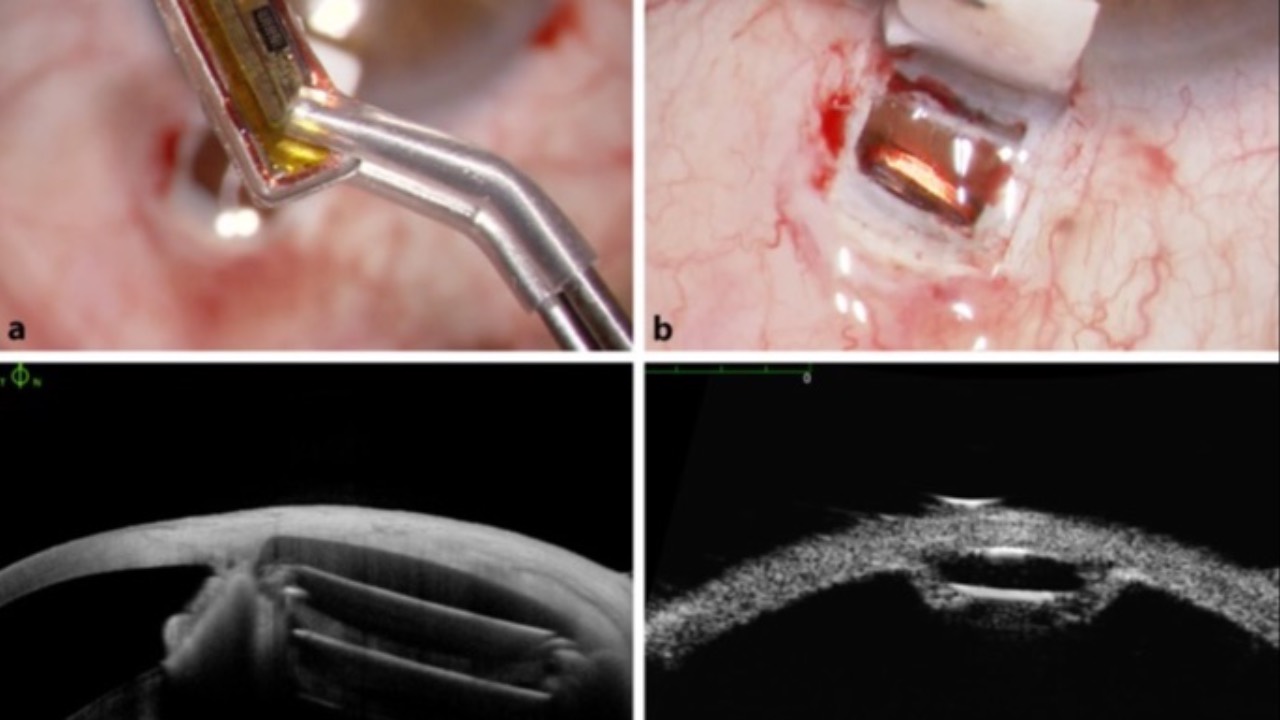

A recent case control study looking at rates of glaucomatous visual field progression before and after the onset of atrial fibrillation found important outcomes for us to consider.

Longitudinal results and meta-analyses found a significant change in visual fields following a diagnosis of atrial fibrillation. The increased progression rates post-onset are most likely linked to micro-thrombi leading to compromised ocular perfusion and ischemia. Additional risk factors include older age, hypertension, and diabetes.

These findings have important clinical implications for us, suggesting early detection and management of atrial fibrillation may help preserve visual function with our glaucoma patients. Perhaps more frequent visual field testing and OCT imaging is now justified, including our glaucoma suspects. We are also reminded of the importance to provide a multidisciplinary approach when managing individuals with or at risk of atrial fibrillation.